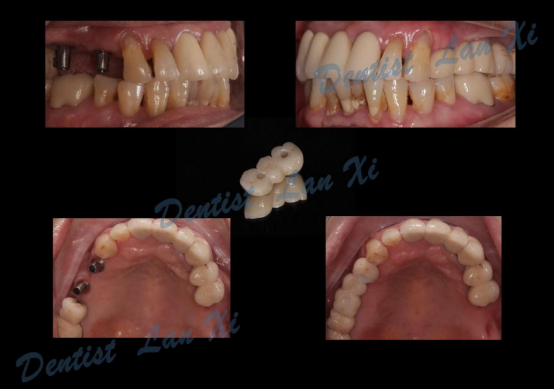

一、以终为始 更精准

在数字化种植导板下,通过CBCT、口扫等途径获取口腔三维信息内容。使患者在种植之前就可以了解到种植方案的相关细节,清晰地看到牙齿修复之后的模拟展示图,提前预知种植术后的效果。

二、精准控制 更安全

在数字化种植导板下的外科手术更加精准。种植体植入方向、位置、角度、深度等一目了然,即可将种植体精准植入到最佳位置,获得更优异的临床效果,手术安全性更高。

除此之外,数字化种植导板还可实现以修复为导向的种植方案设计,使得术后即刻修复成为可能,提高了修复后美学及功能效果的可预见性。